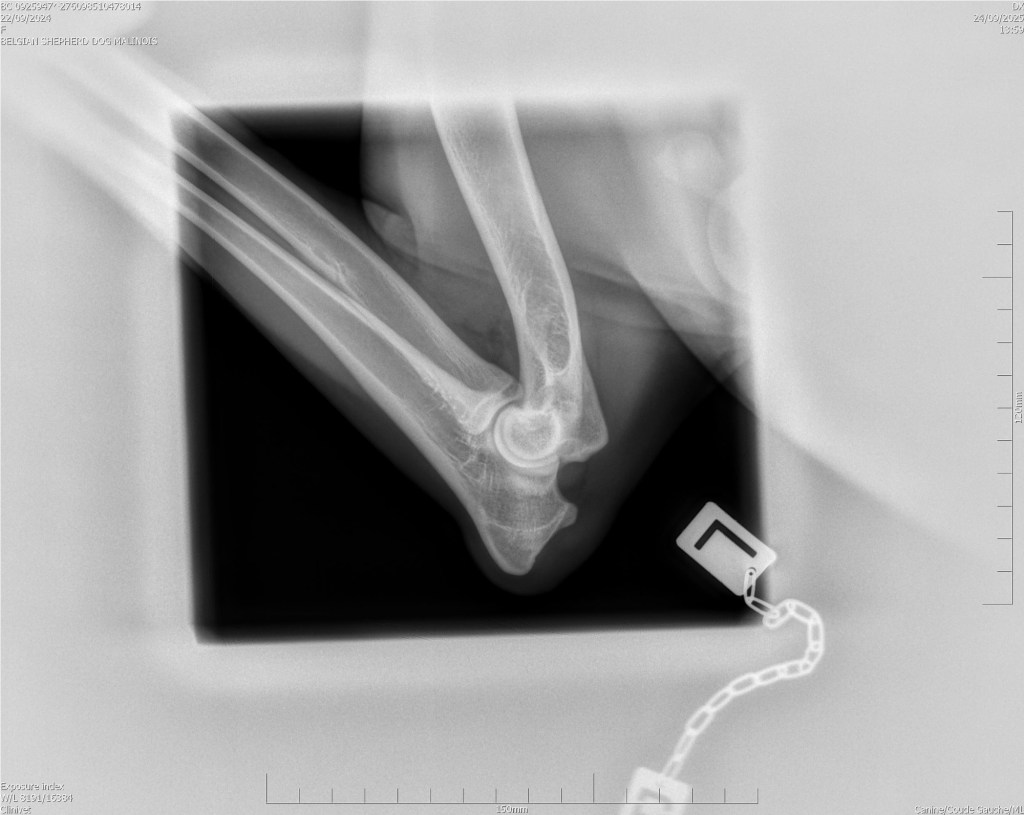

Hips 2/3

Elbows 0/0